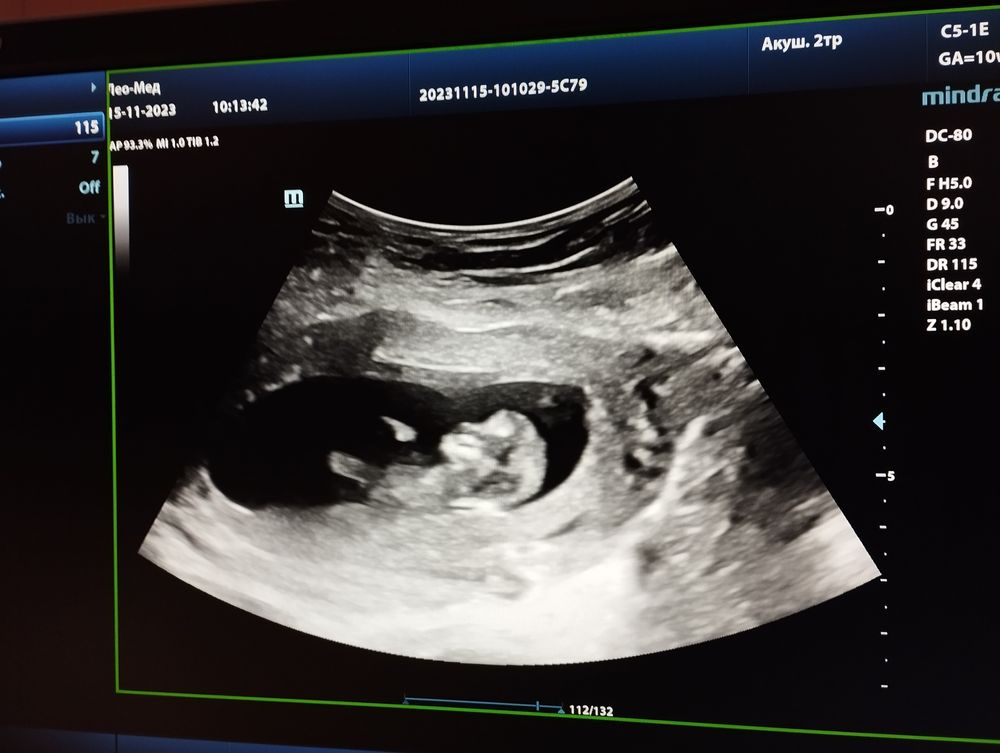

Мы с узи! 🥰💕

Как здорово!)) а какой размер ктр крохи?)

Софья, ктр 49)

Елена, богатырь наверное растет!))) мне послезавтра на узи в 10+1 и тоже интересно сколько уже ктр) в 9+2 был ктр 24мм. Сегодня вот доплером сердечко слушала))

Софья, наверное богатырь точно) у меня все дети маленькие, я сегодня аж опешила, когда узистка сказала 🙈 Про доплер тоже долго думала, но что то решила не брать) тут уже скрининг скоро, потом пол узнавать пойду, так и пролетят недели)

Елена, ого, какие вы большие для своего срока) опережаете)) поздравляю)) врач-узи в жк и видео сняла мне и отправила) каждый день смотрю, как он барахтается, ручкой машет🥰

Елена,У меня в 12-13 недель ктр был 61мм,почти на неделю опережала на первом скрининге,на втором скрининге срок ровно как по мес.Врач мой считает как по первому скринингу 25-26 недель на данный момент.Чсс был 168

Какие замечательные новости с утра! 😍 Такой милый лапусик))) видимо, будет крупненьким. Пусть растёт здоровым!🙏❤ Очень похож на мальчика, удивлюсь, если окажется, что это девочка🤭

Катюнечка Солнышко, я тоже в уверенности что мальчик) с самого начала беременности) не знаю почему)))